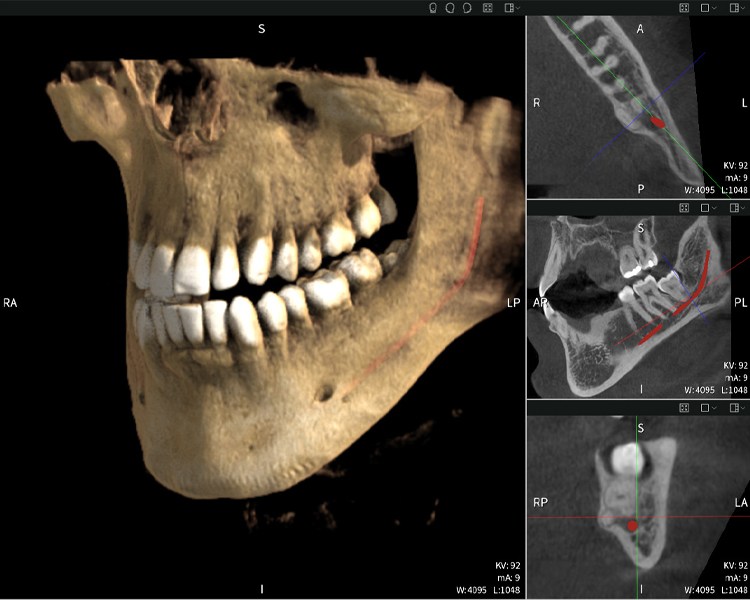

Nachstehend finden Sie einen Fall von Dr. med. dent. Oliver A. Centrella, in dem die CBCT-Aufnahmen mit Seethrough Max entscheidende Informationen zur komplexen Anatomie sowie zur kritischen Beziehung zwischen den Weisheitszähnen und dem Nervus alveolaris inferior lieferten. Bei diesem Fall besteht eine Indikation zur chirurgischen Entfernung der Weisheitszähne.

Abbildung a: Bildgebungsergebnisse von Seethrough Max vor einem schwarzen Hintergrund.

Abbildung a

• Oben links: Axiale Schnittansicht des linken Unterkiefers (Region 38) mit Darstellung des Nervus alveolaris inferior (rot) in unmittelbarer Nähe zu den Wurzeln des Zahns 38.

• Oben rechts: 3D-Rekonstruktion des gesamten Unterkiefers zur Orientierung. Der rot markierte Nervus alveolaris inferior verdeutlicht seine Lage im Kieferknochen.

• Unten links: Sagittale Ansicht des Unterkiefers (Region 38), die die enge räumliche Beziehung zwischen den Wurzeln und dem Nervenkanal verdeutlicht.

• Unten rechts: Koronale Ansicht des Unterkiefers (Region 38) entscheidend für die Beurteilung der räumlichen Lage der Wurzeln zum Nerven.